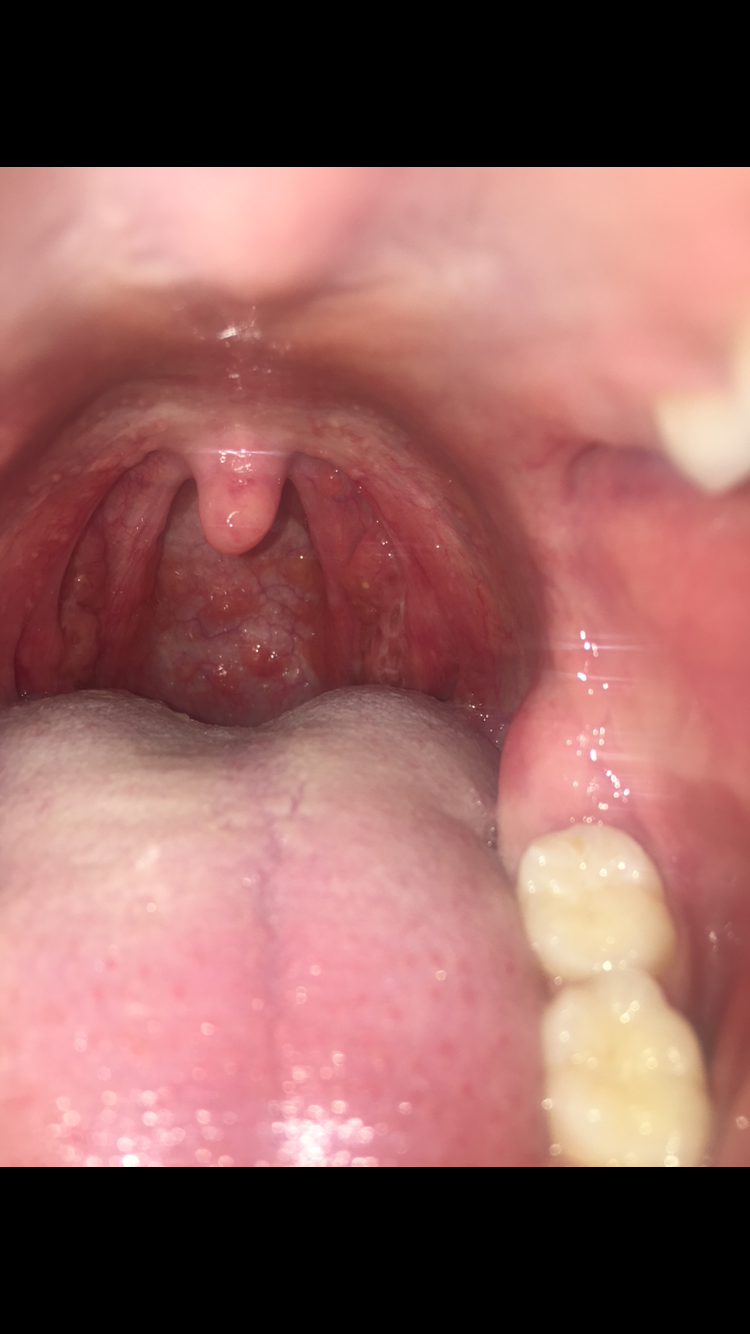

Buonasera a tutti, ecco il mio problema: ho ricevuto sesso orale (e non praticato) e potrei aver contratto una mst come gonorrea e/o clamidia (ho avuto un leggero bruciore nella minzione ultimamente). C'è la possibilità che (inavvertitamente) io mi sia messo le dita in bocca, dopo aver toccato i miei genitali a distanza di qualche giorno... comunque ho avuto dopo poco tempo le placche alla gola e una leggera febbre. Mia madre è medico di famiglia, e mi ha prescritto una terapia antibiotica a base di cefixima (400 mg al giorno x 7gg), ovviamente ignara del sesso orale. Le placche e la febbre sono scomparse nemmeno due giorni dopo dell'inizio della cura. Mi è rimasta una fastidiosa faringite, ho la gola arrossata con dei piccoli "rigonfiamenti", zone leggermente sopraelevate, e questa situazione persiste da circa una settimana dal termine della terapia. Ora ho anche una zona arrossata piatta sul palato (accanto ai molari superiori), non so se c'entri qualcosa. Cercando su internet ho letto che difficilmente il batterio della clamidia si trasmette con questa modalità (attraverso le mani) ...quindi mi domando cosa possa essere (magari streptococco? o un'infezione virale). Sono passate ormai due settimane dal primo mal di gola.

Vi allego delle immagini, non so se potete visionarle. Grazie mille per la vostra disponibilità.

Commento file: 7 giorni fa

Commento file: oggi

Penso che la sua preoccupazione sia per i piccoli rigonfiamenti presenti sulla parete del faringe. Si tratta di alterazioni di frequente riscontro e non le ritengo espressione specifica di una malattia. Se il patner è persona sana penso che non ci sia motivo di preoccupazione. cordiali saluti